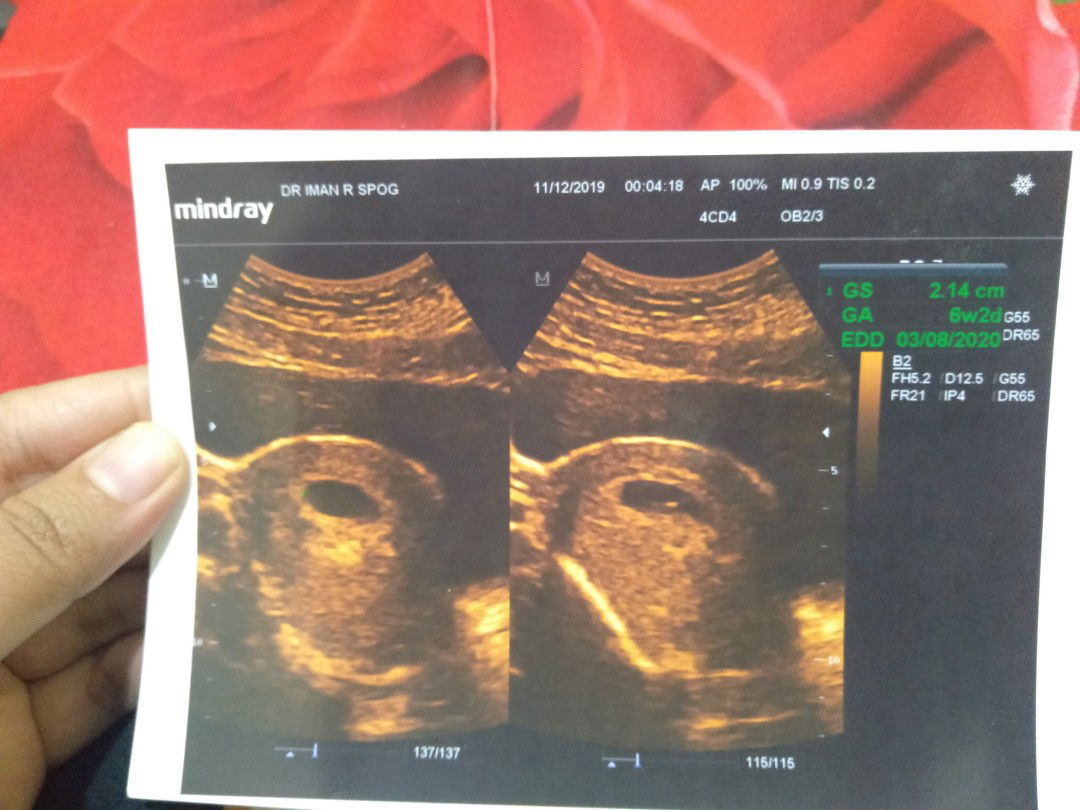

Halo bunda,saya nikah bln agustus kmren. sebelum nikah,saya cek kandungan ternyata ada kista 6cm.. kata dokter kalo gak op akan sulit punya anak. Sy coba mnum herbal2 an. Saya haid 17 oktober, sampek 28 nov gak haid2 lalu saya tespek trnyata garis 2. Udah seneng bangett. Pas periksa kata dokter masih kantung. Suruh balik lg 2 minggi kedepan. pas balik lg tgl 10 des kmren, tetep terlihat masih kantung kosong terlihat ada titik doang gitu ?? kata dokter seharusnya umur kandungan 8w tp gak normal blm kelihatan janin gni. tapi di hasil usg tertulis 6w2d. dokter nyuruh balik lg 2 minggu lg. Kalo gak berkembang, terpaksa harus di kuret karna itu adalah BO atau kandungan kosong. Lgsung lemes rasanya? apakah bunda2 dsni ada yg pernah mengalamin? mohon share bun?